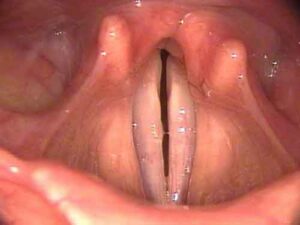

http://www.youtube.com/watch?v=lOJAWOK1RTs Realizzato un gel che promette di riparare le corde vocali danneggiate. Si tratta di un materiale sintetico prodotto da...